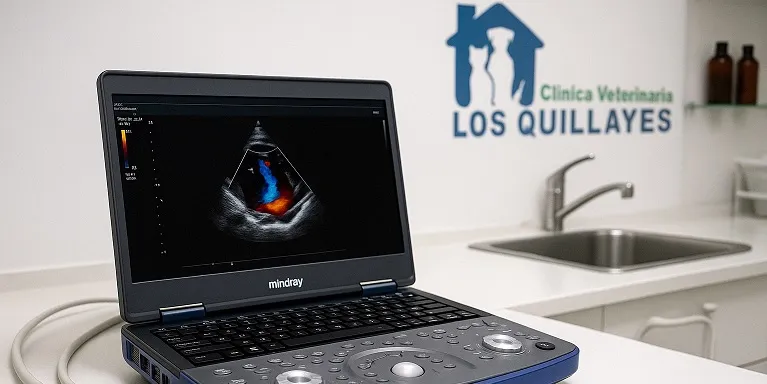

Consultas especializadas en cardiología veterinaria, incluyendo ecocardiografía, electrocardiografía y monitoreo de presión arterial para un diagnóstico certero y un tratamiento adecuado en cada caso.

Estudio detallado del corazón con tecnología especializada. Realizamos ecocardiografías a domicilio o en la clínica, según disponibilidad de agenda y requerimientos del paciente.

Es una evaluación detallada del corazón mediante ultrasonido. Permite diagnosticar problemas cardíacos como soplos, insuficiencia cardíaca o enfermedades congénitas. Nuestro equipo portátil permite hacerlo en tu casa sin estrés para tu mascota.